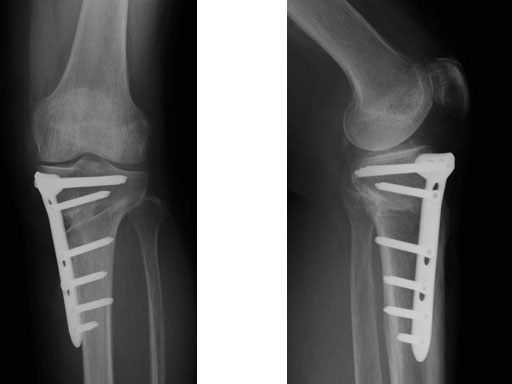

65-year-old female. Osteoarthritic patient complaining of medial knee pain of her left knee.

Case provided by Takeshi Sawaguchi, Toyama, JP

Follow-up in this case is short, because the TomoFix small only became available in August 2008.